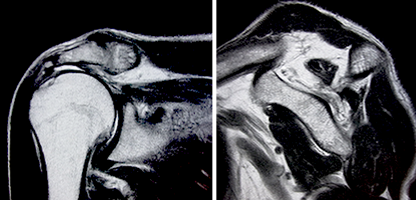

修復可能な腱板断裂。腱の断端は少ししか短縮していない。

筋肉はわずかに白い脂肪に置き換わっているのみである。

修復不能腱板断裂。腱板断裂は大きく内側に短縮している。

筋肉は小さくなり、大部分が白い脂肪組織に置き換わっている。